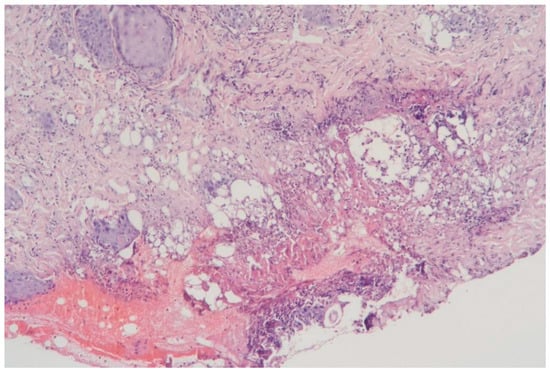

3.1.2. Clinical Case 2: Soft Tissues in the Dissection Area, 15 W (See Figure 3)

Description: During the histological examination, the epidermis and dermis were found to be in a state of subtotal necrosis, with the formation of a demarcation zone infiltrated abundantly with polymorphonuclear leukocytes. The infiltrate extended into the subcutaneous adipose tissue. The vessels in the necrotic area were coagulated, while those in the underlying tissues were markedly dilated. There were no signs of hemorrhage. The appendages of the underlying skin tissues remained intact, and the collagen fibers were preserved.

Figure 3.

Skin changes in Rat 1 on the 7th day after exposure to the thulium laser at 15 W, 75 Hz. H&E staining, 10× objective magnification.